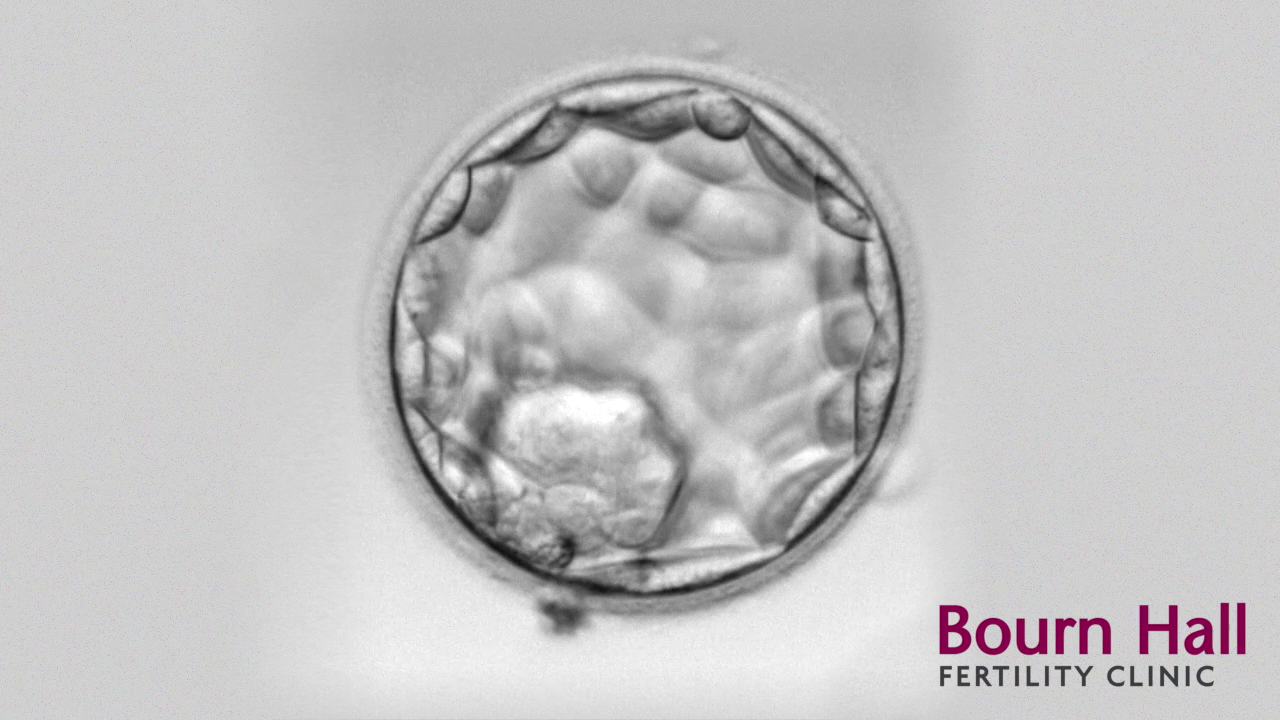

One of the developments that has increased success rates is transferring five-day embryos called blastocysts. This has been made possible by improvements in the culture media, the liquid that surrounds the embryos while they are in the lab.

After eggs are collected and mixed with sperm in the lab, the developing embryos are kept in dishes filled with drops of culture media. Improvements in the media now allow the embryos to grow up to five days, reaching blastocyst stage. This is when the cells start to differentiate, half becoming the baby and the rest the placenta.

In natural conception it is at this point that the embryo would reach the womb, with the lining thickening to receive it.

Not all embryos will reach the stage of blastocyst in the lab and a decision may be made to transfer the embryos earlier. These embryos can still result in a pregnancy and for some patients it might be a better option. This is the type of decision where the experience of the embryologist is invaluable.